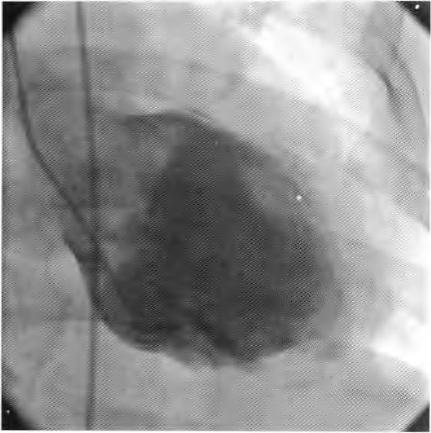

患者择期于10月25日行冠状动脉介入治疗,术前常规给予地塞米松10 mg静脉注射,右侧桡动脉穿刺成功后,经鞘管送多功能造影导管至主动脉窦部,对比剂选择碘帕醇(商品名:碘必乐),导管“吾烟”后数秒钟,患者血压骤然降低至50/30 mmHg,心率逐步增快至90次/min左右,予羟乙基淀粉130/0.4氯化钠注射液(万汶)加压快速静脉滴注100 mL,反复3次静脉注射多巴胺3 mg,血压65/40 mmHg左右,约3 min后心率降至40次/min左右,监护示室性逸搏心律,继之心跳、呼吸骤停。持续胸外按压,气管插管机械通气,持续静脉泵入肾上腺素0.2仙g/(kg•min),并间断4次静脉注射肾上腺素0.5 mg,血压维持在105/50 mmHg左右,进一步行左室造影,见图1。以及左冠状动脉造影,见图2。氧饱和度降至75%,考虑对比剂致高敏反应,引起过敏性休克,静脉滴注甲泼尼龙500mg,经右侧股动脉路径行主动脉内球囊反搏术(intra.aortic balloon pump,IABP)治疗,同时联系外科、麻醉科、体外循环科经左侧股动脉一股静脉行体外膜肺氧合(extra—corporeal membrane oxygenation,EC—MO)支持治疗。ECMO置人后将患者由导管室转送至冠心病监护病房(coronary care unit,CCU)继续抢救治疗,床边心脏超声,见图3。提示室间隔水肿(厚度1.53 cm)。在置人ECMO初期维持绝对镇静,下调直至停用血管活*药性**物,心律以室性逸搏心律为主(持续约48 h),偶然有室速、室颤发作,未作处理。在置人ECMO第3天因急性肾衰竭行床旁连续静脉静脉血液滤过(continuous veno—venous hemofiltration,CVVH)治疗,第4天后患者心率、血压稳定,复查心脏超声提示左心室射血分数40%,撤除ECMO,此后依次拔除气管插管、撤除IABP以及停止CVVH等治疗,患者恢复良好,于11月14日出院。

图1 左室造影未见造影剂外渗至心包腔。心室几无收缩

在冠状动脉介入诊疗术中发生心脏骤停,对于尚处于心肌梗死(尤其是急性ST段抬高型心肌梗死)急性期的病例,要首先考虑心肌梗死后机械并发症(如心室游离壁破裂、室间隔穿孔等)、冠脉急性血栓栓塞事件以及医源性冠脉损伤等,并迅速行相关检查措施排查,如能排除以上危重情况,则要考虑对比剂导致过敏性休克。该患者术中左室造影排除心室游离壁破裂,左冠状动脉造影排除左主干或左冠血管急性血栓栓塞事件以及医源性冠脉损伤,再结合患者存在药物(多种抗生素)过敏史,因此,诊断对比剂致过敏性休克明确。后期心脏超声提示“心肌水肿”,亦是器官组织对过敏的一种表现。